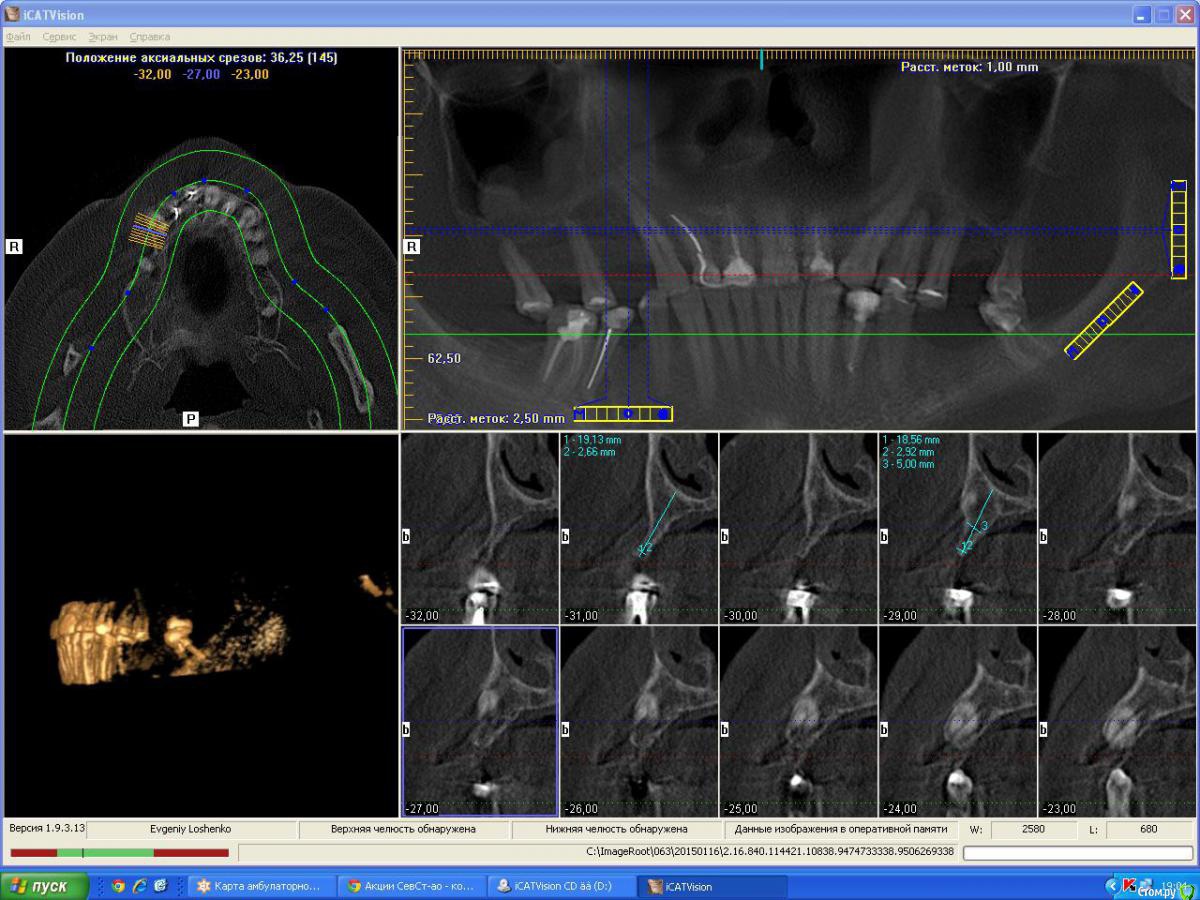

denis1987 Опубликовано 25 февраля, 2015 Поделиться Опубликовано 25 февраля, 2015 Вот такой вот пациент , с адентией в 1 , 2 , 3 и 4 сегментам. Фото прилагаются. Ссылка на комментарий

denis1987 Опубликовано 25 февраля, 2015 Автор Поделиться Опубликовано 25 февраля, 2015 Вот ничего другого на ум не приходит как аугментация костными блоками аутогенными, по крайней мере в 1 и 3 сегментах. Во 2м егменте расщепление + закрытый синус, в 4м вроде как хороший аэродром. Интересует мнение форумчан. Ссылка на комментарий

Aquarius Опубликовано 25 февраля, 2015 Поделиться Опубликовано 25 февраля, 2015 (изменено) Ну в области 14-го ламина точно сработает. И Вы планируете аугментацию на неправильно выставленных срезах!!! Изменено 25 февраля, 2015 пользователем Aquarius Ссылка на комментарий

Aquarius Опубликовано 25 февраля, 2015 Поделиться Опубликовано 25 февраля, 2015 область 26. Срез не захватывает полностью гребень. Не знаю,может я ошибаюсь. Ссылка на комментарий

denis1987 Опубликовано 25 февраля, 2015 Автор Поделиться Опубликовано 25 февраля, 2015 Денис,когда планируете аугментацию? Если не в ближайшие несколько дней, то я постараюсь выложить отпротоколированный кейс с ламиной в области 14. Может что-то возьмете на вооружение. Вроде наконец учёл все ошибки)) И что-то выросло.Все , я понял про что вы говорили в плане среза , на самом деле кусок альвеоляра не влез , настроил норм , но все равно картина не сильно изменилась к сожалению ( Ссылка на комментарий